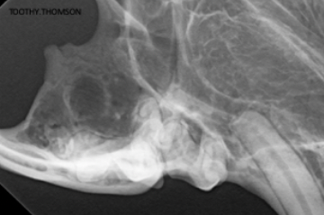

The biggest challenge to the bisecting angle simplification are the canine teeth. This is because while the rest of our patient’s dentition have similar angles between the crowns and roots, the canine teeth do not. (Figure 6a and Figure 6b)

Instead of using the angle of the crown for the canine tooth, the angle of the rostral mandible should be used. This is because the root of the canine tooth follows that curvature. (Figure 7a and Figure 7b) Canine teeth are a bit of an anatomical exception, given their crowns and roots do not have the same angle, you need to use the root angle to get the correct bisecting angle.